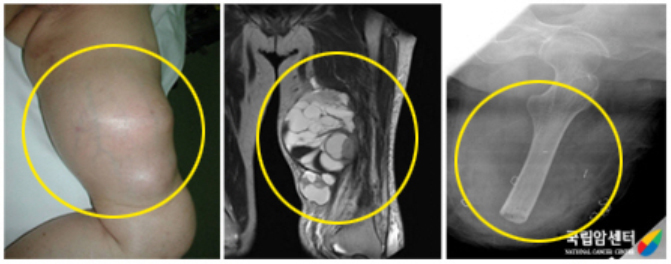

이 종양은 진행이 느리기는 하지만 결국 폐에 전이됩니다. 종양의 부분 절제나 주위 조직을 불충분하게 절제한 경우 수개월에서 1~2년 이내에 대부분이 재발됩니다. 원발 부위 재발이 없는 경우나 절단 치료 후에도 종종 폐에 전이되는 것으로 보아 활막 육종의 전이는 비교적 초기에 일어난다고 생각할 수 있습니다. 따라서 활막 육종은 광범위 절제술 후 항암제 투여 및 방사선 치료가 재발 및 전이를 억제하는 데 도움이 될 수 있습니다.

[ 왼쪽 무릎관절 주위에 발생된 활막육종 환자의 사진 ]

연부조직 범위와 종양의 골 침범 정도를 알기 위해서 자기공명영상(MRI)검사가 유용합니다. 폐의 전이에 대해서 알 수 있는 흉부 방사선사진과 전산화단층촬영(CT)은 종양의 병기를 결정하는데 필수적인 검사입니다. 원격 전이는 진단 당시 3~10%로 보고되며 대부분 폐로 전이됩니다.

국소 재발은 10~40%로 보고되고 진단 후 2~3년에 잘 일어납니다.